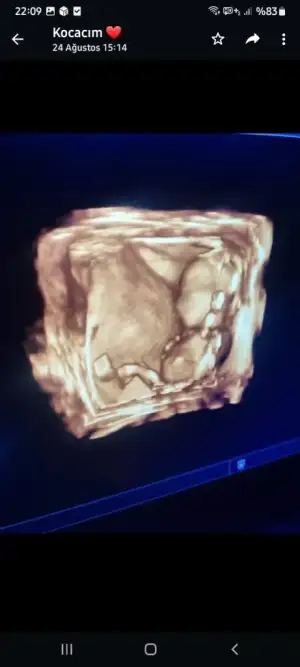

Çok teşekkür ederim görüşün içinUc cizgi gordum ben bence kiz

İnşallah benim de gönlüm kızdan yana tabiki evlat evlattır sağlıklı gelsin inşallah çok sağol düşüncen için

Nub çıkıntısı çok görünmüyor ama kıza benziyo canımMerhaba hanımlar 13 haftalık bizede tahmin yapar mısınız :)

TeşekkürlerNub çıkıntısı çok görünmüyor ama kıza benziyo canım

Bunlar da bu günden, inanın o çıkıntının ne olduğunu bile bilmiyorumNıb çıkıntısını göremedim canım

Ayy kıza bwnziyo dudakları var 3 çizgi ama değişirmi bilemem sağlıcakla al kucağına canım şuan kaç haftalıksınBunlar da bu günden, inanın o çıkıntının ne olduğunu bile bilmiyorum

Canım burda bebiş kaç haftalık kıza benziyor nub teorisine göre 3 çizgi var 12 haftalıktan sonra şekillenmeye başlıyor biraz ama inşallah gönlündekini nasip eylesin rabbim sağlıkla sıhhatleBana da yorum yapabilir misiniz rica etsem

Bende o ultrasonda 12+2 deydim şuan 14+3 dün cinsiyeti öğrenmek için gittik biraz haylaz çıktı doktoru çıldırttı tam göstericekken kapatıyor çok da hareketli inşallah enerjisi anne karnında biterde doğunca uğraşmazsın dedi bakalım 2 hafta sonra 3lü tarama var birde o zaman bakarız dediAminn inşallah çok teşekkür ederim 10+2biliyo musun doktor da kıza benzetti ama net bi şey de söylemedi

12 haftalık, 3 çizgi nerde görünüyor acabaCanım burda bebiş kaç haftalık kıza benziyor nub teorisine göre 3 çizgi var 12 haftalıktan sonra şekillenmeye başlıyor biraz ama inşallah gönlündekini nasip eylesin rabbim sağlıkla sıhhatle

Buna da bakar mısınızUc cizgi gordum ben bence kiz

%85 erkek gibiMerhaba hanımlar 13 haftalık bizede tahmin yapar mısınız :)